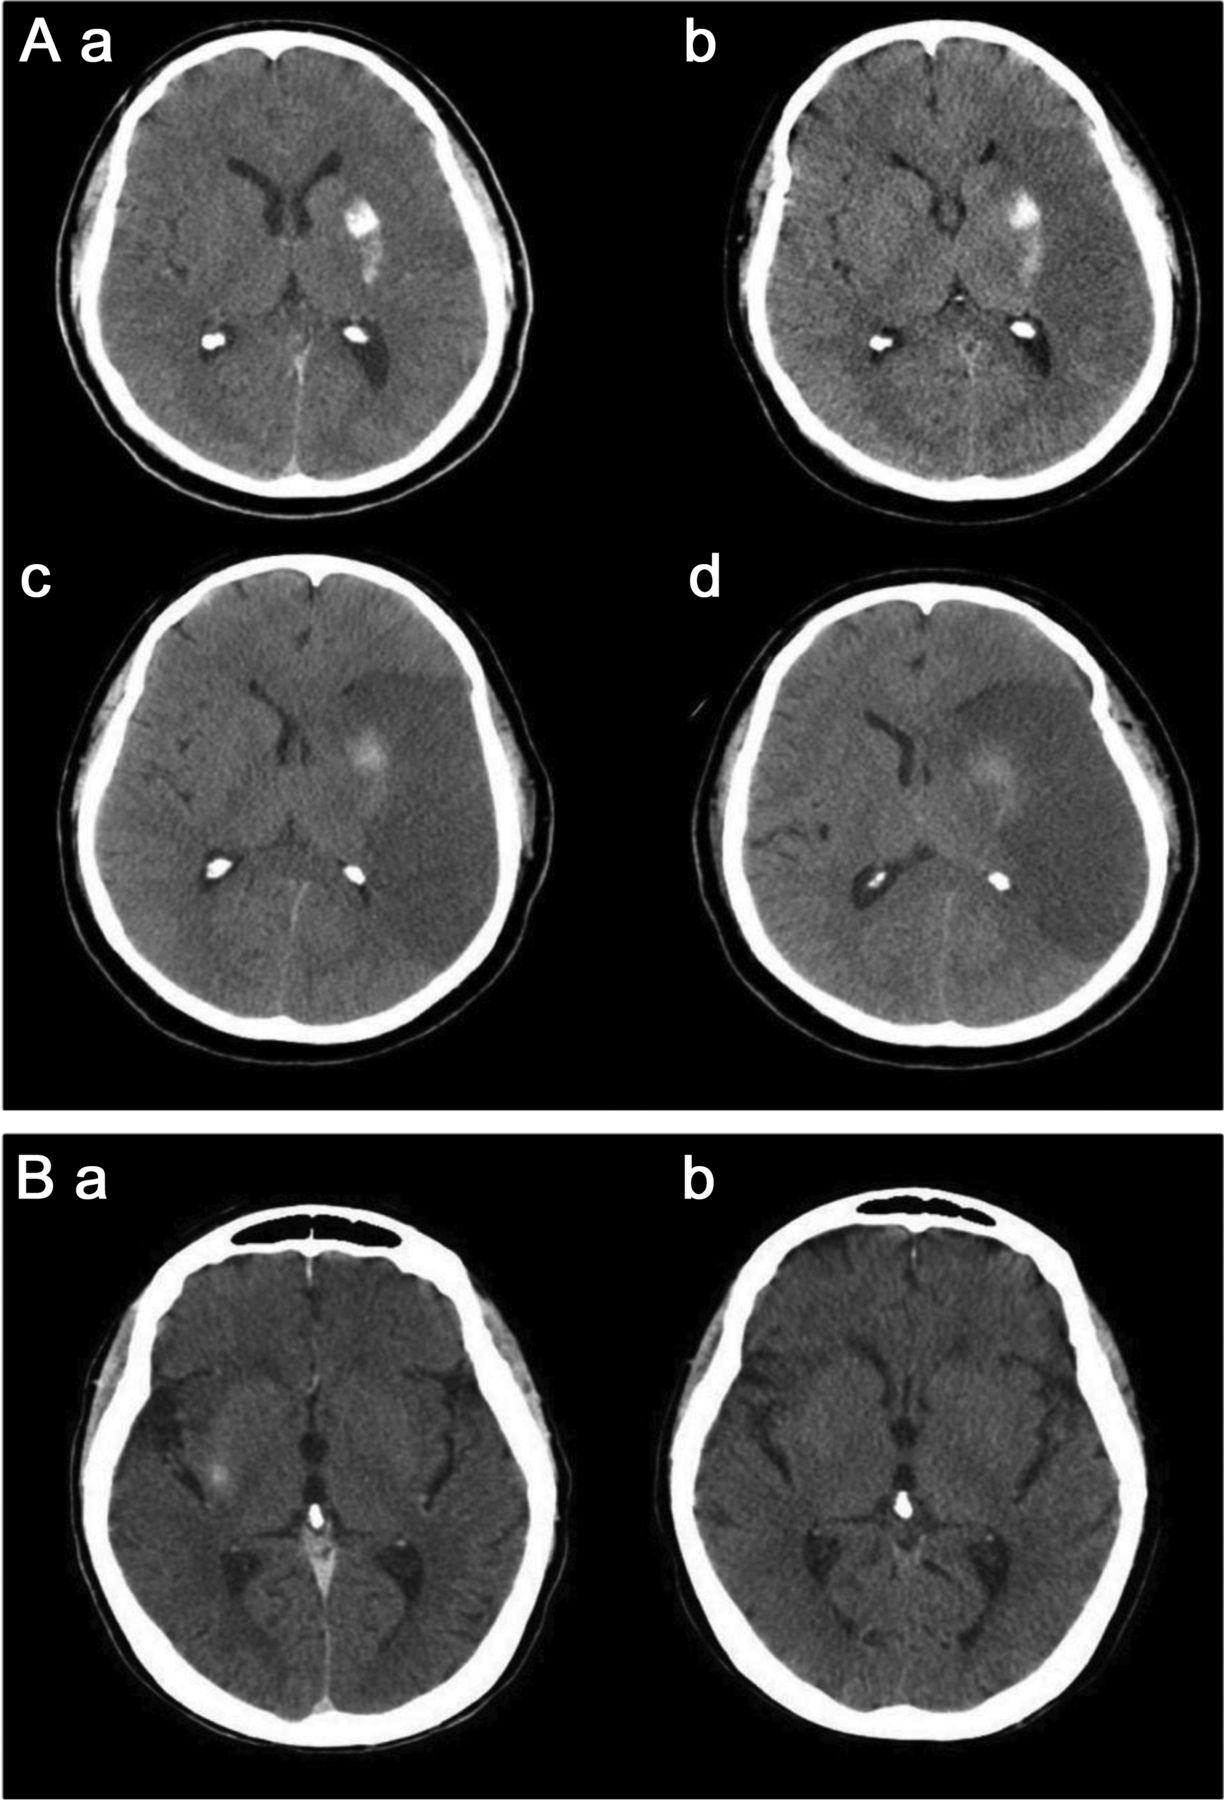

立即后动脉内的溶栓头CT (A)展示了一个新领域内的hyperdensity离开豆状核(A)。十四个小时postprocedure头部CT显示持久hyperdensity,损失的灰白色分化在左parieto-temporal凸性,并抹杀左侧侧脑室CT扫描主管(b)。随访36小时,60个小时持续hyperdensity左壳,建议外渗与脑水肿和中线移位(c, d)。头部CT动脉内的溶栓后立即(b)显示了一个hyperdensity正确的硬膜(A),解决完全重复头上CT表现16小时postprocedure (b),显示对比度增强。

几个机制假设对比造影剂外渗和出血有关。19最有说服力的毒性在基板,包括对比BBB的结构性障碍与干扰。它导致溢出的血液细胞元素从微血管,反过来,导致对比外渗(定义为hyperdensity暗示对比[Hounsfield单位> 90])在24小时(图4A)。相比之下,对比度增强是由于从血管造影剂泄漏到细胞外空间,由于BBB的渗透性增加。头部CT二次的hyperdensity对比度增强通常在24小时内清理(图4B)。对比溢出已被证明有一个强大的协会与HT以及预后不良。20.